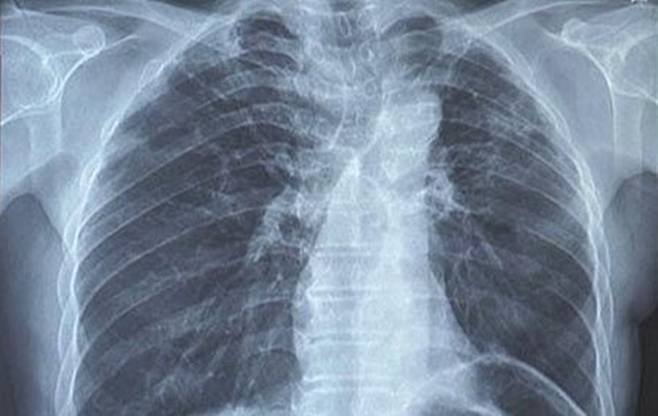

폐암은 우리나라에서 세 번째로 많은 암이다. 사망률 1위에 해당하는 병이지만 초기에는 특별한 증세가 없어 일찍 발견하기 쉽지 않다.

폐암 환자의 75%가 잦은 기침을 호소하는데 증상이 감기와 비슷해 자각하기 어렵다. 때문에 환자의 절반 가량이 다른 장기에 전이된 4기에 암이 발견되는 경우가 많다.